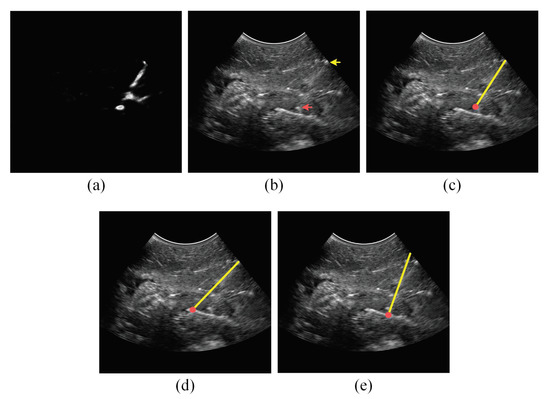

2.2. Analyzing the Power Doppler Ultrasound Image to Obtain an Initial Estimation of the Needle Axis and Identify the Candidate Regions of the Needle

2.3. Analyzing the B-Mode Ultrasound Image to Obtain Accurate Localization of the Needle Axis

2.4. Analyzing the Power Doppler and B-Mode Ultrasound Images to Obtain Accurate Localization of the Needle Tip